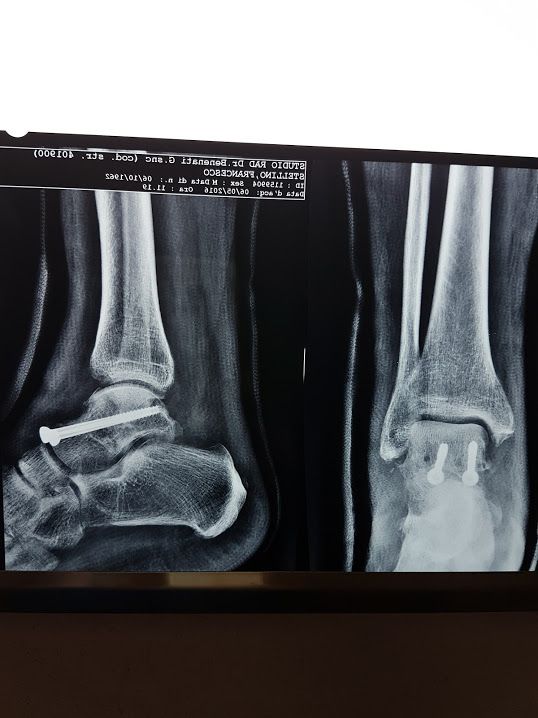

Foto e video